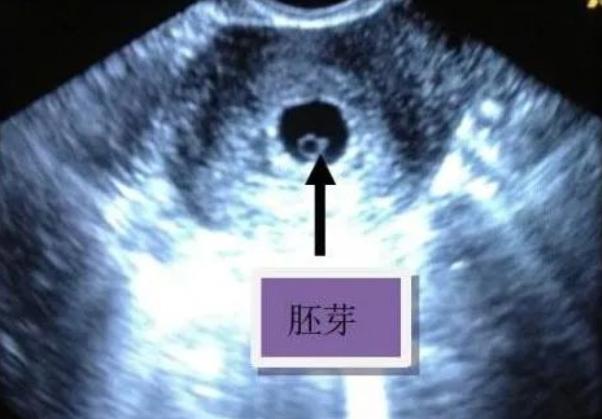

胚胎早期B超往往先看到卵黄囊,这时孕囊还小,还没有发育出胎心胎芽临床上大多规定见卵黄囊后2周之内要见到胎心胎芽,如果见卵黄囊2周以后还没有胎心胎芽,诊断胚胎停育,要给予及时清宫终止妊娠胚胎停育诊断要慎重,不能诊断过早临床上常有胚胎停育诊断过早的情况,比如卵黄囊出现以后没有;特殊人群需更早进行B超检查例如,高龄孕妇有过胎停育史的孕妇等,因胚胎发育风险较高,建议提前进行B超检查,以便及时发现异常并采取干预措施总之,有卵黄囊后胎芽和胎心的出现时间受多种因素影响,需结合个体情况综合判断若有疑问或担忧,应及时咨询医生,并保持良好心态,注意休息和营养,为胚胎。

卵黄囊出现后,胎心胎芽通常在怀孕56周出现,但具体时间因人而异影响胎心胎芽出现时间的因素月经周期若女性月经周期较长,排卵和受孕时间会推迟,导致胎心胎芽出现时间相应延后例如,周期为35天的女性可能比周期28天的女性晚1周左右观察到胎心胎芽受孕时间受孕时间较晚时,胚胎可能尚未发育到;相关事项怀孕早期卵黄囊胎芽和胎心是B超观测孕囊已内的重要结构,这三个结构在怀孕早期是判断孕囊生长发育的重要指标,只有先出现卵黄囊期后才有可能出现胎芽和胎心,进而判断孕囊是否存活正常情况下,一般在怀孕六周左右就应该能看到卵黄囊,出现了卵黄囊以后必须在一定的时间以内出现胎芽和胎心正常情况。

胎芽胎心出现时间有卵黄囊后,胎芽和胎心一般会在78周时出现如果看到卵黄囊,说明是宫内孕,此时可以等待两周后再复查B超,以观察胎芽和胎心的发育情况建议检查时间从末次月经来的那天开始算起,建议产妇在78周左右去做B超检查,这时可以明确看到是否为宫内孕,以及是否有胎芽和胎心因此,如果。